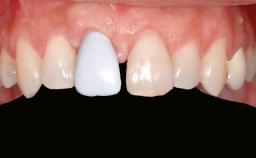

Shell Technique for Horizontal and Vertical Maxillary Bone Augmentation in a Partially Edentulous Patient with Aggressive Periodontal Disease

Prosthesis Type FDP

Patient's Esthetic Expectations Low Medium High

Lip Line No exposure of papillae Exposure of papillae Full exposure of mucosa margin